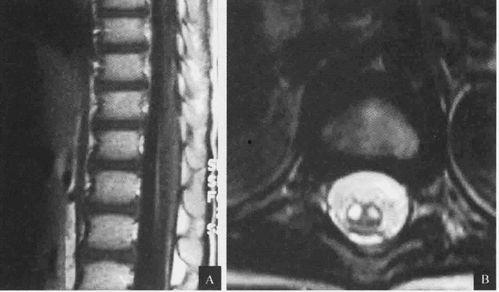

脊髓炎,一个听起来就让人心生恐惧的词汇。它是一种罕见的神经系统疾病,主要影响脊髓,导致患者出现不同程度的瘫痪。或许,你曾在网络上看到过一些关于脊髓炎的视频,但你是否真正了解这些患者的生活呢?

脊髓炎的治疗方法有很多,主要包括药物治疗、物理治疗和康复训练等。